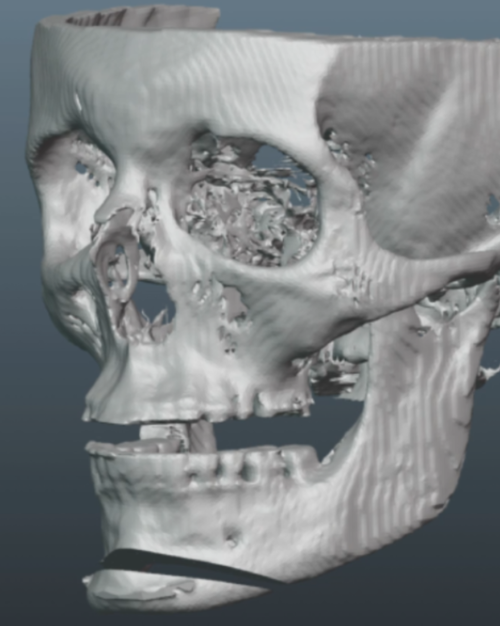

Old silicone wraparound:

Old silicone wraparound: